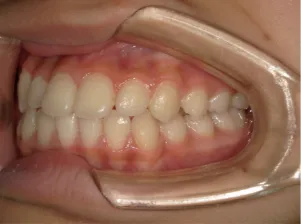

治療中⑦中3:15y5m 口元・咬合の改善で抜歯治療スタート

治療中⑧高1:15y11m 抜歯治療中

治療中⑨高2:17y1m 抜歯治療中

治療後⑩高2:17y7m 抜歯治療終了